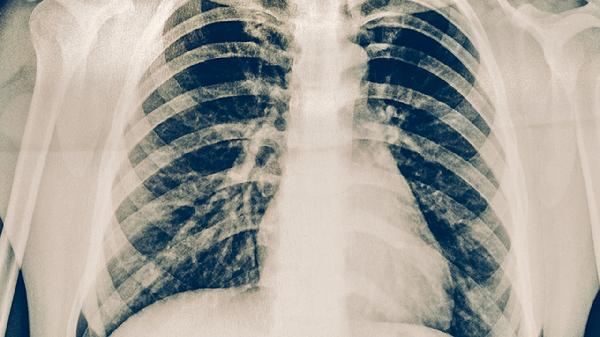

肺結核早期癥狀缺乏特異性,容易與其他呼吸道疾病混淆。建議出現(xiàn)上述癥狀持續(xù)2周以上時及時就醫(yī),進行胸部X線、痰涂片、結核菌素試驗等檢查。日常生活中應注意保持室內通風,加強營養(yǎng)攝入,適當鍛煉增強體質。確診肺結核后應嚴格遵醫(yī)囑完成全程規(guī)范治療,避免擅自停藥導致耐藥性產生。密切接觸者應進行結核篩查,高危人群可考慮預防性治療。